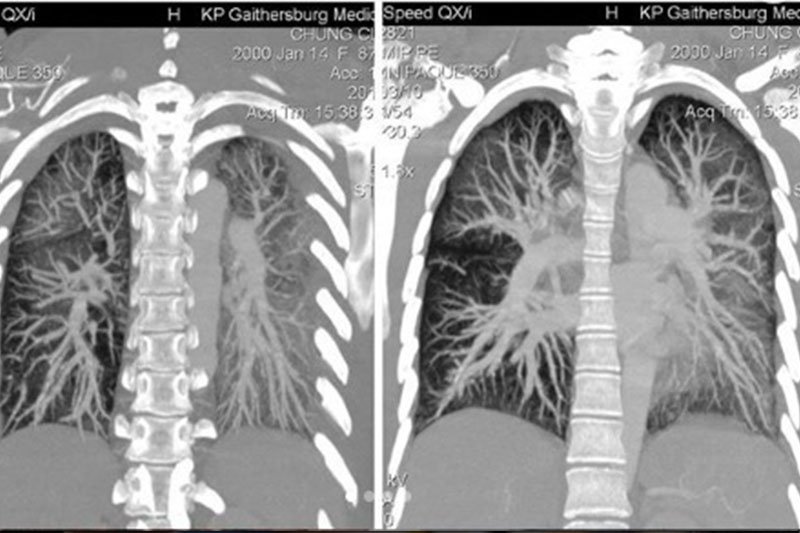

電子煙壞處|少女長期吸食電子煙 致肺部組織嚴重受損